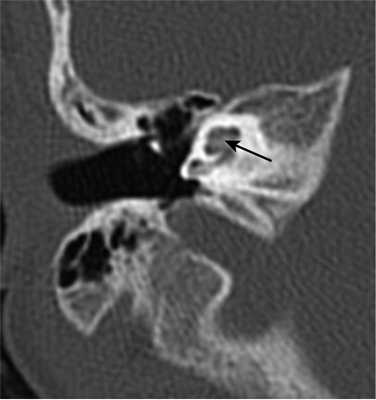

Рис. 1. КТ, аксиальная проекция. Облитерация улитки (стрелка).

Шваннома лицевого нерва: осевое КТ-изображение (костное окно) демонстрирует расширение ганглия, присутствует однородная масса мягких тканей (стрелка)

Хроническое воспаление среднего уха с холестеатомой: коронарная КТ показывает боковой свищ полукруглого канала (стрелка), вызванный эрозией кости из-за роста новообразования

Хроническое воспаление среднего уха: осевая КТ демонстрирует очаговую кальцификацию (стрелка) в барабанной полости - тимпаносклероз.